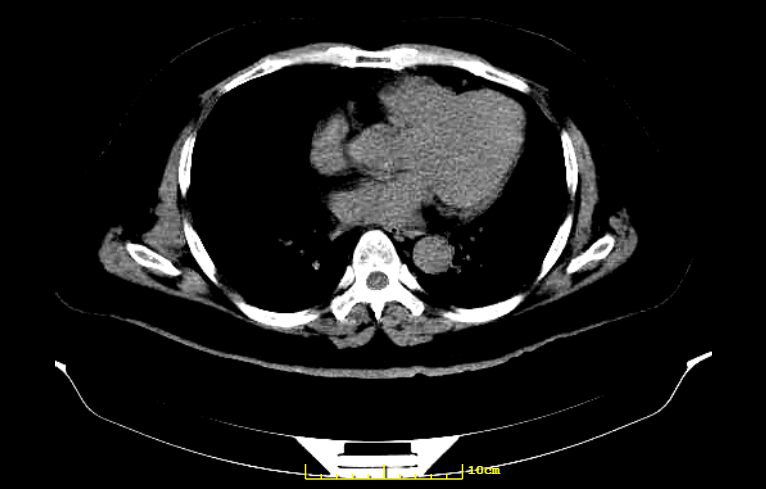

然而初步查体后,李先生的血压竟高达183/96mmHg!进一步的CT结果显示,李先生颅内大量出血:

(医生供图)

最终李先生被确诊为左侧基底节区脑出血,伴随高血压病3级(很高危)。